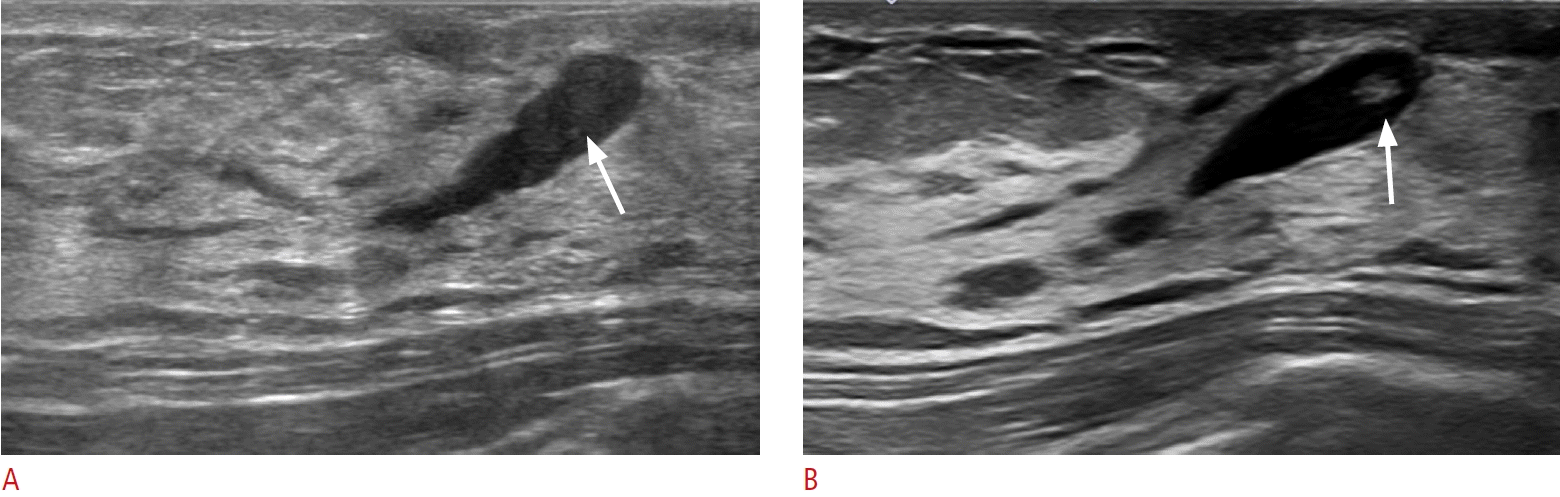

7. Kim WH, Chang JM, Moon WK, Cho N, Yi A, Koo HR, et al. Intraductal mass on breast ultrasound: final outcomes and predictors of malignancy. AJR Am J Roentgenol. 2013; 200:932–937.

9. Guo Y, Raghu M, Durand M, Hooley R. Retroareolar masses and intraductal abnormalities detected on screening ultrasound: can biopsy be avoided? Br J Radiol. 2018; 91:20170816.

27. Yoon JH, Yoon H, Kim EK, Moon HJ, Park YV, Kim MJ. Ultrasonographic evaluation of women with pathologic nipple discharge. Ultrasonography. 2017; 36:310–320.